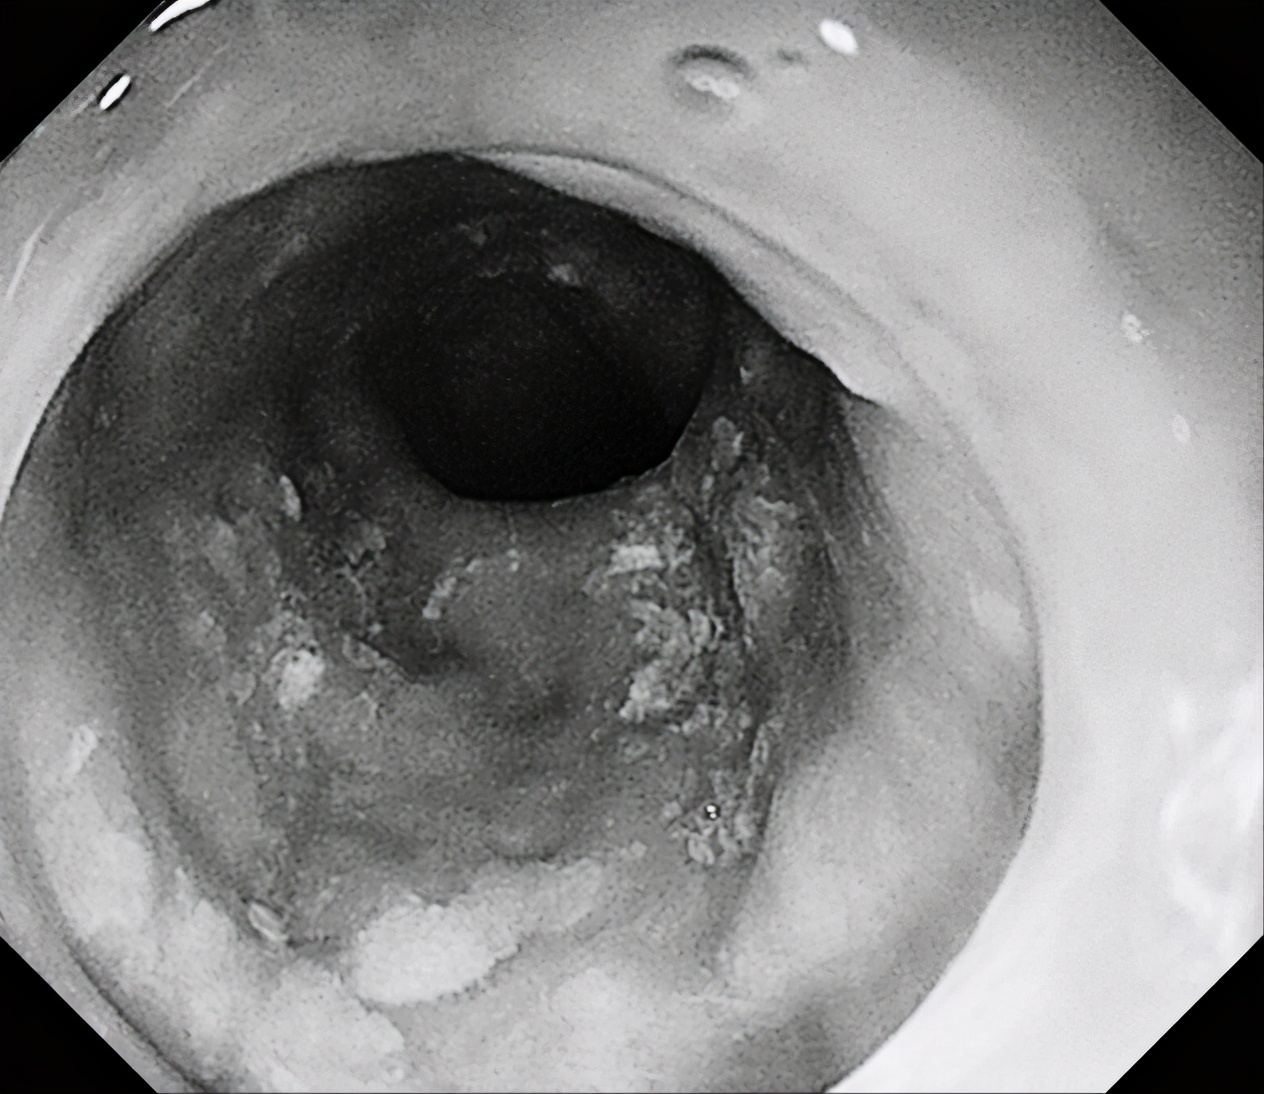

1月6日下午,消化内镜中心张蓉副主任医师为一名患者行胃镜检查时,发现食管中下段黏膜粗糙,覆不均匀少许白苔,粘膜微血管增粗紊乱,行NBI观察及卢戈氏碘染色后发现患者病变呈全周型。

内镜下观察平坦型较多,主要特征:黏液帽(黏液蛋白的缘故)、云雾状外观、扩张的II型腺管(Open II型)、分支扩张、蛇形的血管。当病变出现有蒂或亚蒂、隆起中有隆起、中央明显凹陷、病灶明显发红、合并IIIL、IV、Vi、VN型腺管表现时应想到癌变的可能性。